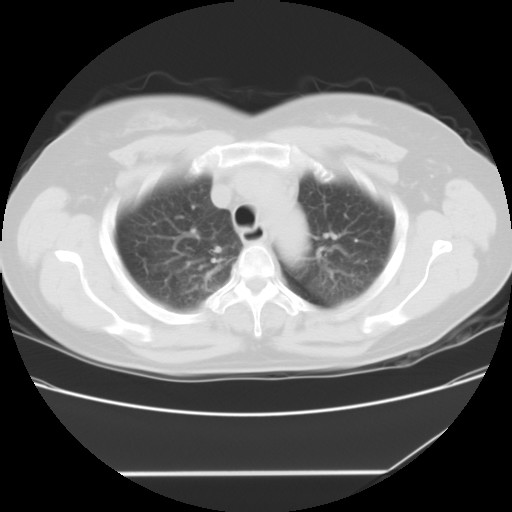

标题: CT24018:女性,62岁,咳嗽4年,无热,胸部CT扫 [打印本页]

女性,62岁,长期咳嗽,既往从事工作有粉尘接触,有高血压病史,110/150mmhg,近日咳嗽加重,脸面浮肿,请大家帮看下,

1、尘肺;2、慢性支气管炎合并肺部感染;3、心影增大(左房、左室大),考虑高血压性心脏病。

慢支并肺部炎症;右肺结核球?主肺动脉、右肺动脉影不宽,右心室不大,不支持肺心病;无心包积液。

间质性肺炎,有纤维化趋势。

1)慢性支气管炎并肺部感染、肺气肿。2)肺间质纤维化。

间质性肺炎,左下肺机化性肺炎。